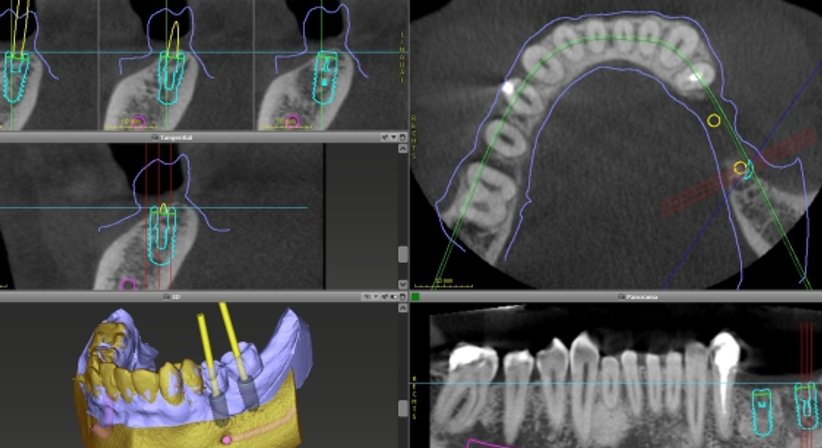

Das 3D-Röntgen (DVT) dient als Grundlage für eine präzise Planung und Implantatsetzung (navigierte Implantologie).

Somit kann

- das vorhandene Knochenangebot optimal genutzt,

- sensible Strukturen, wie z.B. Nerven, Kieferhöhle etc.,geschont und

- das Implantat in einer für die prothetische Versorgung möglichst präzisen Position gesetzt werden.

Zahnimplantate fungieren als Träger und bilden die Basis für festsitzende Kronen oder Brücken. Mit DVT-Daten und der chirurgischen Schablone wird das sichere und präzise Platzieren der Implantate realisiert.